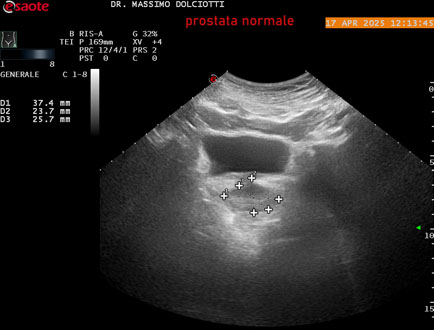

Data inserimento: 01/10/2025

Ecografia del: 17/04/2025

Strumento: Esaote MyLab Eight

Sonda: Convex Multifrequenza 1-8 MHz, Endocavitaria Multifrequenza 3-9 MHz e 3-13 MHz

Età Paziente: M 35 anni

Motivazione dell'esame: disuria.

Commento all'esame: le immagini ed il video documentano la prostata di ecostruttura regolare e morfovolumetria normale con diametro trasversale di 40 mm, diametro anteroposteriore di 21 mm e diametro longitudinale di 43 mm, con volume prostatico calcolato di 18 cc (v.n. < 20 cc), il profilo prostatico è regolare e netto, non si documentano calcificazioni intraghiandolari, la vascolarizzazione della ghiandola è normale. La vescicola seminale destra presenta diametro longitudinale di 44,4 x 7,8 mm, la vescicale seminale sinistra ha diametro longitudinale di 45,3 mm x 7,2 mm.

Conclusioni: prostata normale (normal prostate).